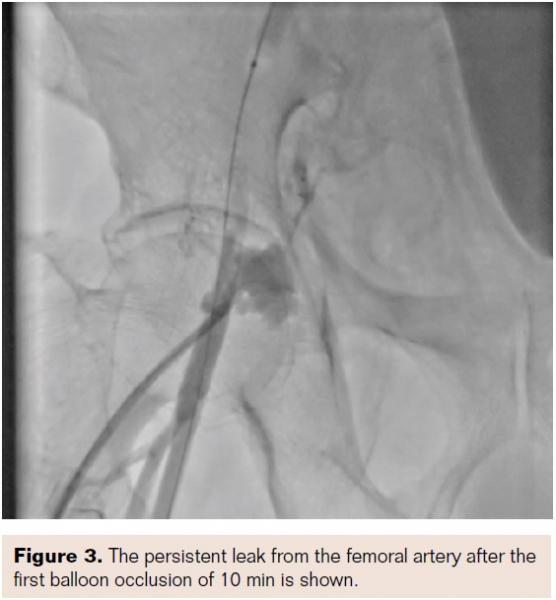

The sheath in the right femoral artery was retained. A puncture was made in the left femoral artery, and a sheath and a 6 Fr RCA catheter was placed in the right external iliac artery; repeat injection showed continued extravasation through the dissection in the common femoral artery (CFA). An exchange-length guidewire was placed in the dissection, and a peripheral balloon was tracked over this and the balloon was inflated over the perforation for 4 atm for 10 minutes (Figure 3). A second check shot showed the extravasation continued. Then, a 0.014˝ BMW guidewire was passed through the femoral access into the extravasation aneurysmal sac.

A glide catheter 4 Fr was threaded over the guidewire, and gel foam mixed with contrast was injected into the aneurysmal sac (Figures 4 and 5).